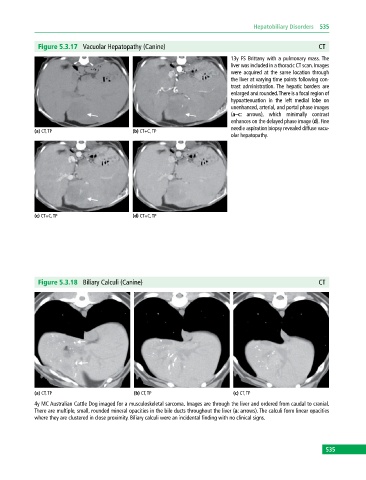

Figure 5.3.17 Vacuolar Hepatopathy (Canine) CT

13y FS Brittany with a pulmonary mass. The

liver was included in a thoracic CT scan. Images

were acquired at the same location through

the liver at varying time points following con-

trast administration. The hepatic borders are

enlarged and rounded. There is a focal region of

hypoattenuation in the left medial lobe on

unenhanced, arterial, and portal phase images

(a–c: arrows), which minimally contrast

enhances on the delayed phase image (d). Fine

needle aspiration biopsy revealed diffuse vacu-

(a) CT, TP (b) CT+C, TP

olar hepatopathy.

(c) CT+C, TP (d) CT+C, TP

Figure 5.3.18 Biliary Calculi (Canine) CT

(a) CT, TP (b) CT, TP (c) CT, TP

4y MC Australian Cattle Dog imaged for a musculoskeletal sarcoma. Images are through the liver and ordered from caudal to cranial.

There are multiple, small, rounded mineral opacities in the bile ducts throughout the liver (a: arrows). The calculi form linear opacities

where they are clustered in close proximity. Biliary calculi were an incidental finding with no clinical signs.